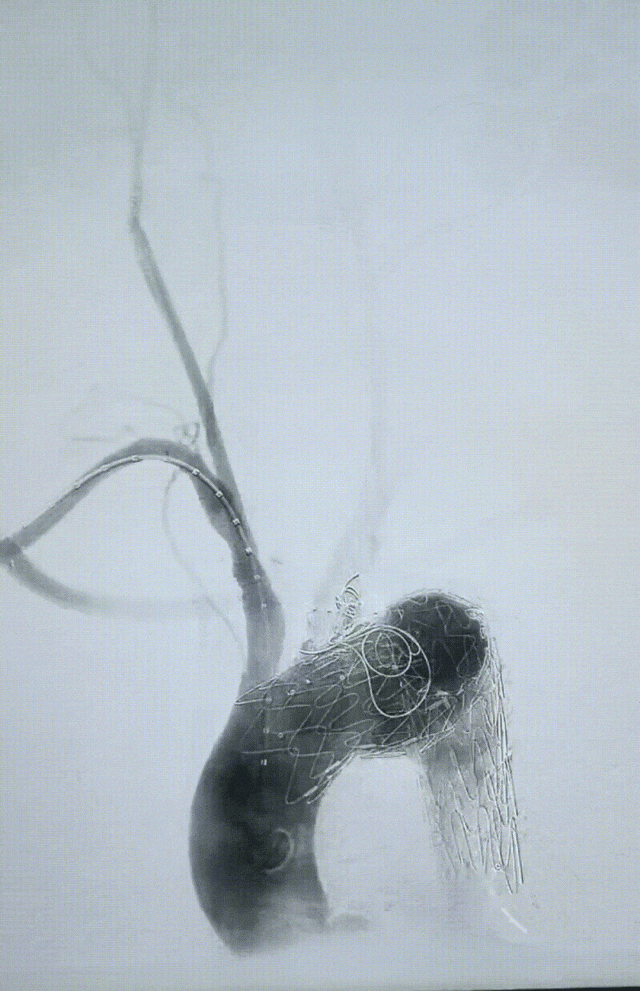

术前先完成LSA转流,术中DSA造影,明显可见弓部病变情况,巨大主动脉瘤近端累及LCCA

释放主体支架并用分支支架重建LCCA后造影,贴壁良好,但由于瘤体过大且偏前侧,有少量I型漏出现

覆使用弹簧圈填塞后再次确认,瘤体隔绝良好,无内漏,效果满意!